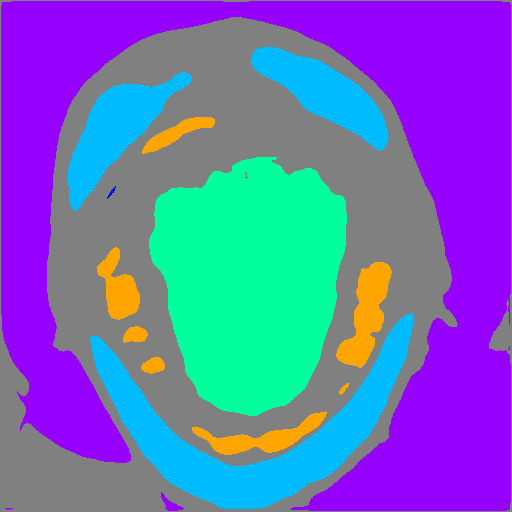

Refer to caption Refer to caption Refer to caption

Multi-class learning One-class positive-only learning (Ours) Multi-class positive-only learning

Figure 1: Decision boundaries of different learning settings. Colored markers represent positive data in different classes. “?” represents unlabelled data. Our proposed framework forms a multi-class positive-only learning setting which has distinct decision boundaries that aims to enclose positively labelled data for each class and can thus serve as an OOD detection mechanism based on non-enclosed areas.

3.2 Positive-only learning for multi-class segmentation

We start by illustrating the concept of positive-only learning. Figure 1 shows various decision boundaries with the presence of unlabelled data. Conventional multi-class classifiers show no ability to detect outliers within the unlabelled data. Instead, they categorise them into one of the known classes. Alternatively one-class classifiers can highlight outliers in the unlabelled data but they are limited to a single class. In contrast, our proposed method effectively identifies outliers in the unlabelled data while establishing distinct decision boundaries enclosing the labelled positive data for each class.